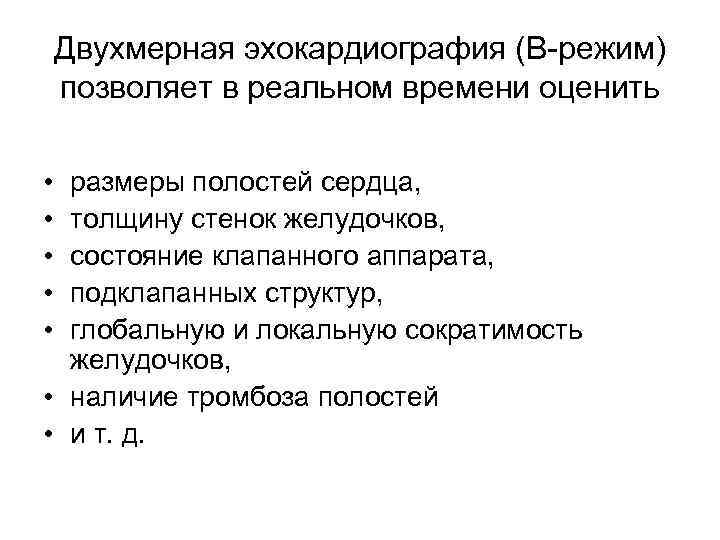

Двухмерная эхокардиография (В-режим) позволяет в реальном времени оценить • • • размеры полостей сердца, толщину стенок желудочков, состояние клапанного аппарата, подклапанных структур, глобальную и локальную сократимость желудочков, • наличие тромбоза полостей • и т. д.

Двухмерная эхокардиография (В-режим) позволяет в реальном времени оценить • • • размеры полостей сердца, толщину стенок желудочков, состояние клапанного аппарата, подклапанных структур, глобальную и локальную сократимость желудочков, • наличие тромбоза полостей • и т. д.